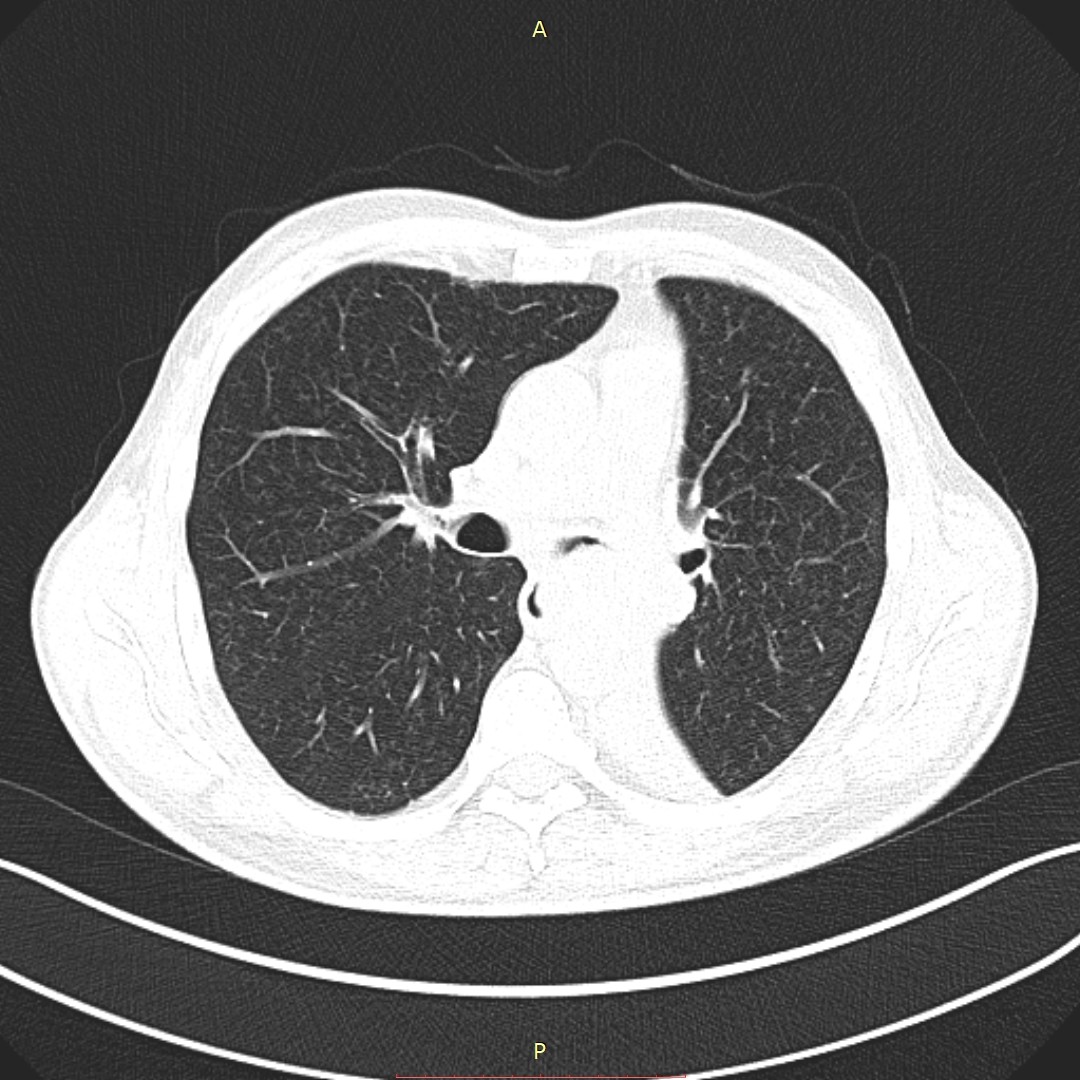

- გულმკერდის კტ (Axial) სტენტირებამდე 5 დღით ადრე

აღინიშნება მარცხენა მთავარი ბრონქის ოკლუზია სიმსივნური წარმონაქმნით